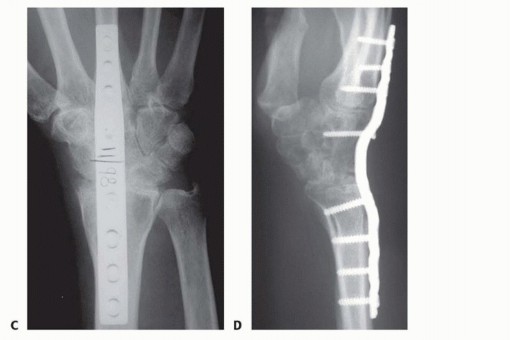

TECH FIG 2 • A,B. Complex wrist collapse secondary to rheumatoid arthritis treated with an intramedullary rod and wiring. Ulnar impaction symptoms developing at the distal radioulnar joint. C,D. Less severe wrist disease in a different patient was treated with a Darrach resection and wrist arthrodesis.(continued)

TECH FIG 2 •(continued)E,F. PA and lateral radiographs after wrist arthrodesis in a different patient with rheumatoid arthritis was undertaken using two Steinmann pins inserted through the second and third and third and fourth intermetacarpal spaces. (A-D: Courtesy of P.J. Stern, MD; E,F: Copyright Thomas R. Hunt III, MD.)